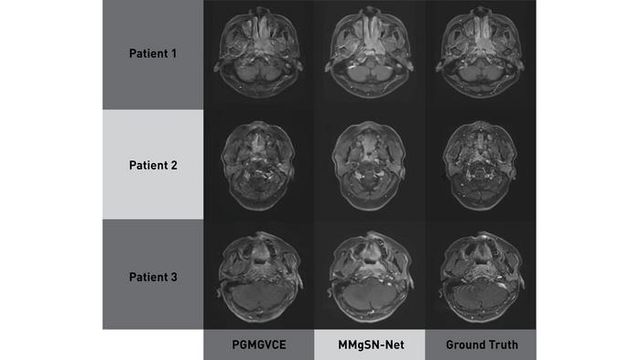

Comparison of brain MRI scans from PGMGVCE, MMgSN-Net, and ground truth showing smoother texture in MMgSN-Net images.

Researchers at The Hong Kong Polytechnic University developed two AI models – MMgSN-Net and PGMGVCE – to create virtual contrast-enhanced MRI scans for nasopharyngeal carcinoma using non-contrast images.